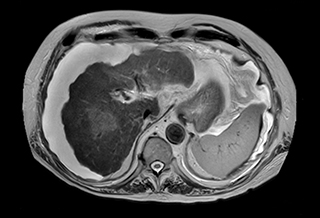

Short breath hold cardiac cine

MCVI Ambition Short breath hold cardiac cine

These are some images of a cardiac cine scan with a short breath-hold time. A high temporal resolution provides a smooth cine, which helps in assessing heart function. Ingenia Ambition.